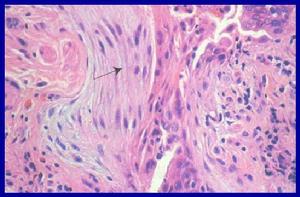

由於目前積累病例數較少,尚未建立本病引起腎損害的病理特徵。不過已見有報導1 例IHES 並發腎病綜合徵患者。 (1).腎活檢 光鏡下可見嗜酸性粒細胞呈廣泛或結節性在腎組織內浸潤,並呈現典型免疫複合物型腎小球疾病的病理改變——毛細血管內增生。免疫螢光可見IgG 和C3 主要在內皮下沉積。電鏡下沉積物呈微管狀結構,直徑大小不等,20~80nm。(2).骨髓活檢 顯示細胞數正常或增多,可見輕度骨髓纖維化,巨核細胞數正常或減少;骨髓塗片上可偶見到Charcot Leyden 晶體,嗜酸性粒細胞平均占髓系細胞的30%。